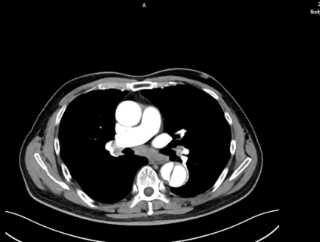

时间就是生命。医生会结合症状,快速进行以下检查:医院会根据CT血管成像(CTA)进行诊断。如确诊为主动脉夹层,则会进行紧急处理,立即镇痛、控制血压和心率(如静脉注射β受体阻滞剂)。

主动脉腔内修复术:微创治疗。通过大腿根部的股动脉,将一个覆膜支架送入主动脉夹层部位,像打补丁一样覆盖住内膜破口,使血流不再进入假腔,促进假腔血栓化愈合。